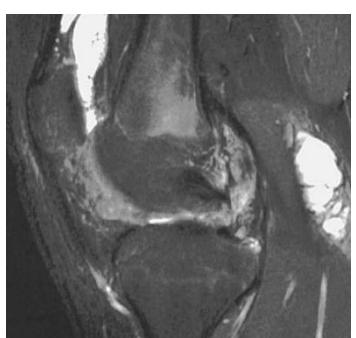

- MRI - local staging, soft tissue involvement

- Local staging (MRI)

site: Distal femur size: matrix: soft tissue involvement: